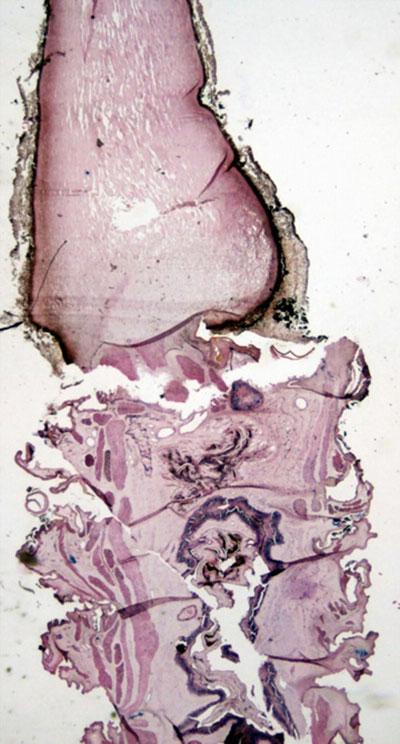

通过关系,我弄到了几根真正的冬虫夏草,外表及切开后的剖面如下图(1、2)。

图1:侧面观,左边是虫右边是“草”

图2:图1的切开观

我将冬虫夏草制成切片,到显微镜下观察一下。(见图3、图4)

图3:下半部是虫体 上半部是“草”